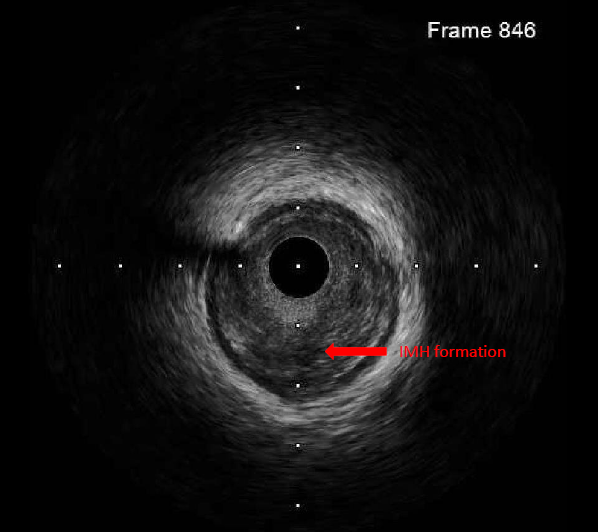

The left coronary artery was engaged with an XB 3.5¡¿6 Fr guide catheter. Using a Fielder FC guidewire with a Fine-Cross microcatheter, the distal LAD was successfully accessed. Pre-dilation with a 1.5¡¿20 mm balloon demonstrated residual stenosis with poor flow. Further dilation with a 2.0¡¿15 mm balloon improved flow. Intravascular ultrasound (IVUS) revealed intramural hematoma (IMH) in the proximal-to-mid LAD. A drug-eluting stent (BMX6 2.75¡¿33 mm) was deployed from the proximal LAD (distal to the first diagonal branch) to the mid LAD, followed by proximal post-stent dilation with a 4.0¡¿12 mm non-compliant balloon at 4-16 atmospheres. Post-deployment IVUS confirmed adequate stent expansion without malapposition. Final coronary angiography demonstrated TIMI grade 3 flow.

By integrating the MDCT coronary anatomy with the three-dimensional electroanatomical map and ablation lesion sites, it was demonstrated that the radiofrequency applications were directly adjacent to the proximal LAD, resulting in thermal injury and IMH formation.

This case underscores that LAD total occlusion can occur as a rare but serious complication of radiofrequency ablation at the anteroseptal RVOT, where the ablation site lies in close proximity to the proximal LAD. The underlying mechanism in this case was not atherosclerotic plaque rupture, but rather thermal injury leading to IMH formation. Importantly, prompt coronary intervention successfully restored coronary flow and preserved myocardial function.